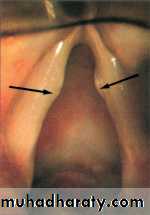

The diagnosis is made at endoscopy with the child breathing spontaneously.Classical appearance include an omega-shaped epiglottis, short aryepiglottic folds and loose redundant mucosa over the arytenoids.

On inspiration, the cartilages are sucked inwards obstructing the airway.